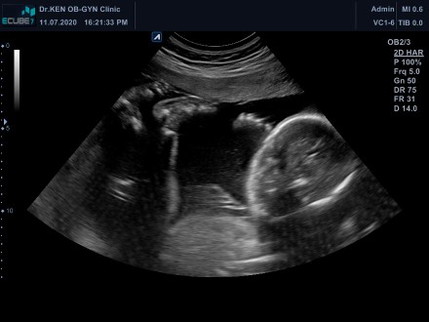

5เดือนแล้วจ้า

ขอเสียงแม่ๆทีมพ.ยหน่อยค่ะได้ลูกสาว/ลูกชายกัน บ้านนี้ลูกสาวค่ะ